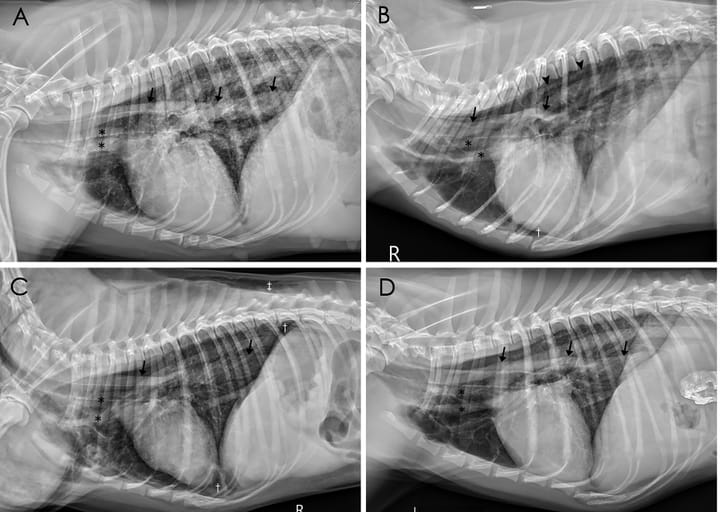

Right (A, B, C) and left (D) lateral thoracic radiographs of Dogs 3, 4, 6, 7, respectively, showing pneumomediastinum. The adventitial surface of the trachea, esophagus (arrowheads), and cranial mediastinal vessels (✽) are visible due to the presence of gas in the mediastinum (A-D). The azygos veins (arrow heads) are also visible (B). Mild pneumothorax († in B, C) and subcutaneous emphysema (‡ in C) were observed.

The most common clinical signs were dyspnea (100%) and anorexia (82%). Pneumomediastinum was the most prevalent radiographic finding (91%), followed by symmetrical increased lung opacity (64%), especially in the caudodorsal lung fields. Other features included pneumothorax (27%), pleural effusion (27%), and subcutaneous emphysema (18%). One case also had pneumoretroperitoneum. All dogs died, either naturally or by euthanasia due to clinical deterioration.